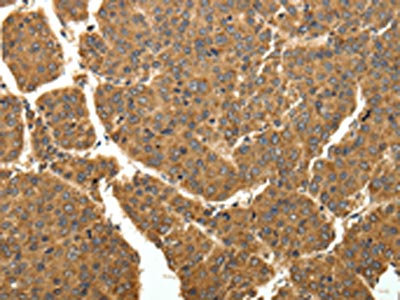

The image on the left is immunohistochemistry of paraffin-embedded Human liver cancer tissue using CSB-PA127898(EIF2AK3 Antibody) at dilution 1/40, on the right is treated with fusion protein. (Original magnification: ×200)